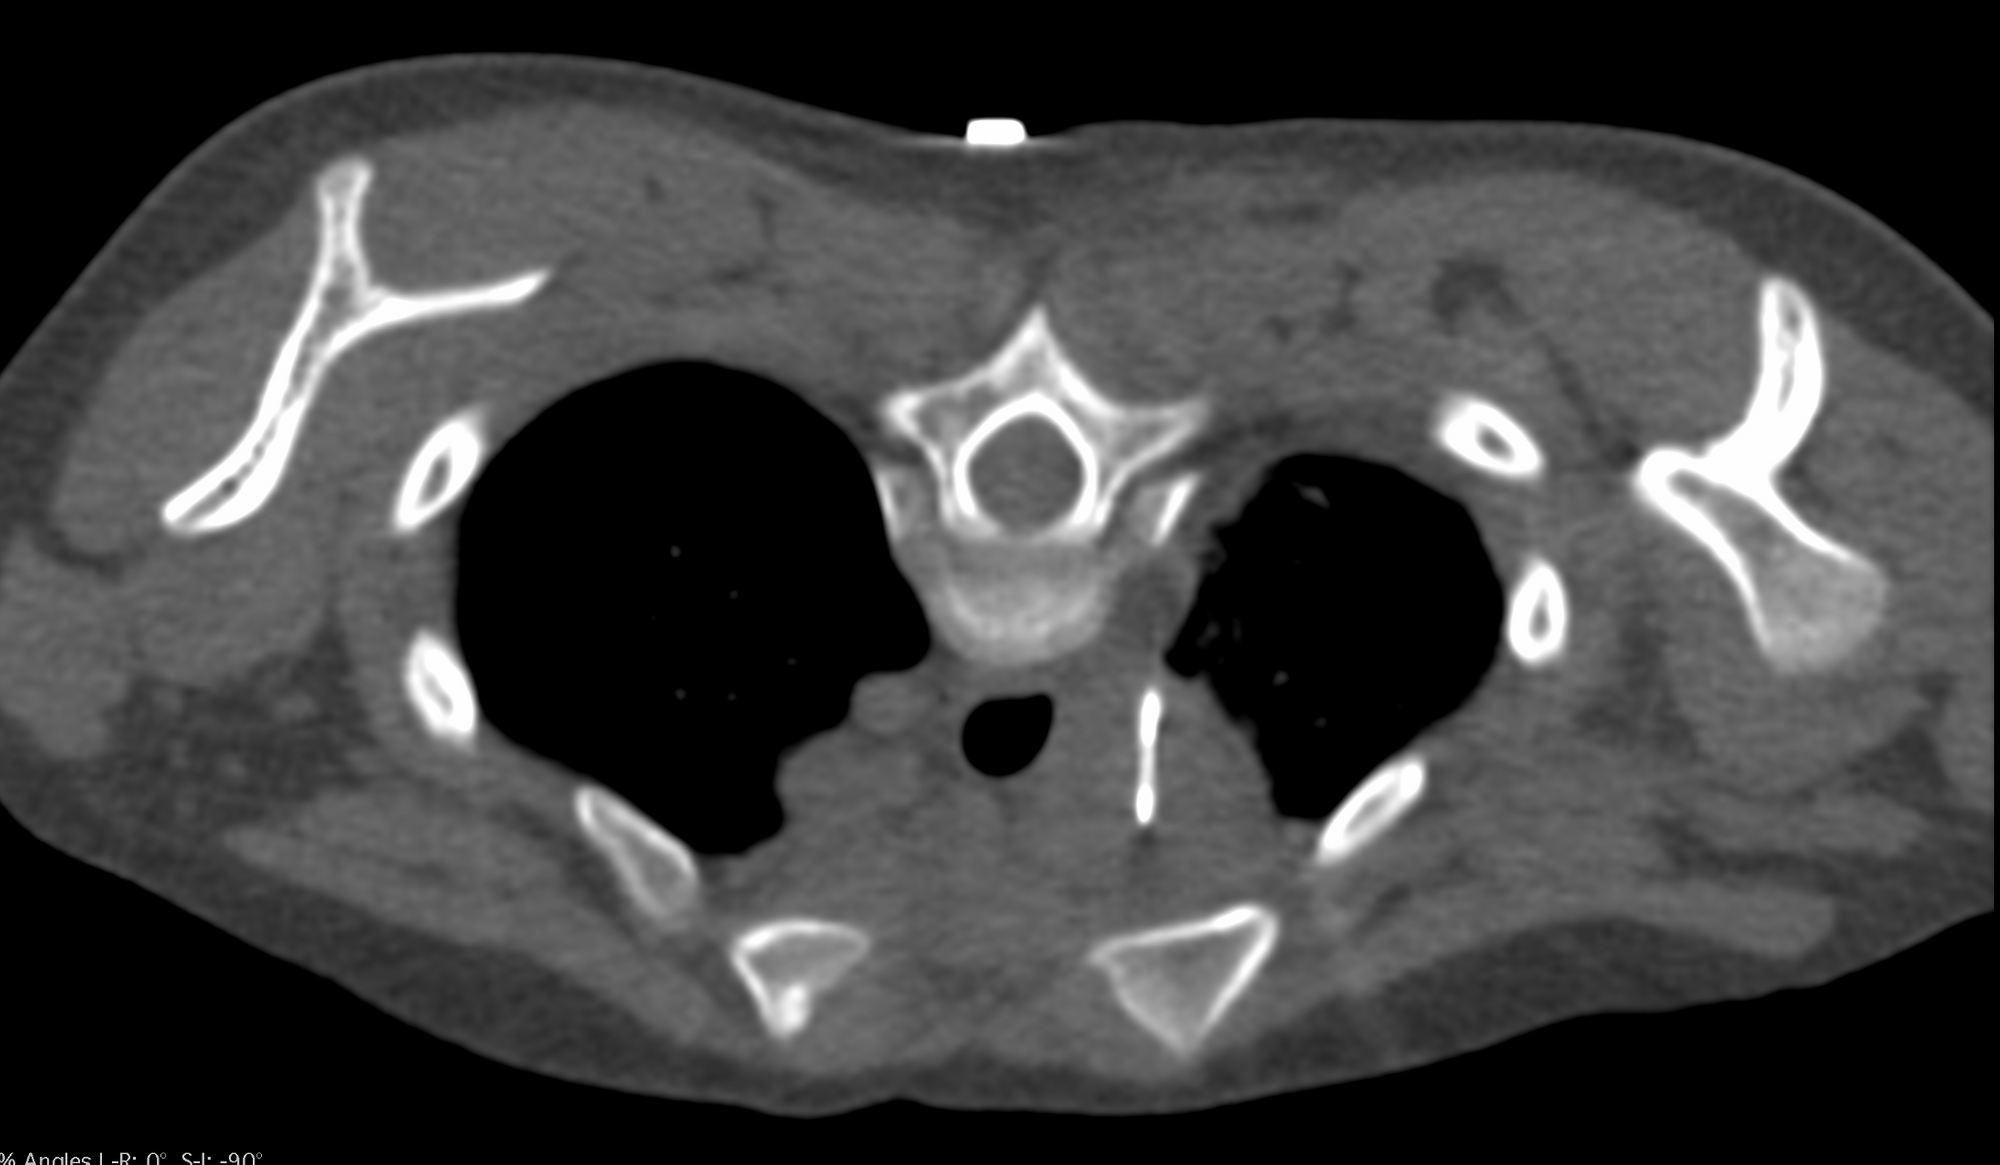

Case 1: Right Paratracheal Node Biopsy - One Stage - Pediatric